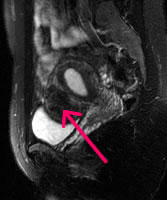

骨盤部MRI

子宮筋腫

ひどい生理痛、貧血あり。MRIを撮ると子宮の下方に4cm大の筋腫が見つかった。

MRIは放射線を使用しないので、 これから妊娠を希望される若い女性の方には特にお勧めできます。

| 骨盤腔MRI | 15,400円 | 排尿痛・残尿感 排尿障害・腰痛 下腹部痛 | 前立腺癌 膀胱癌 前立腺肥大症など |